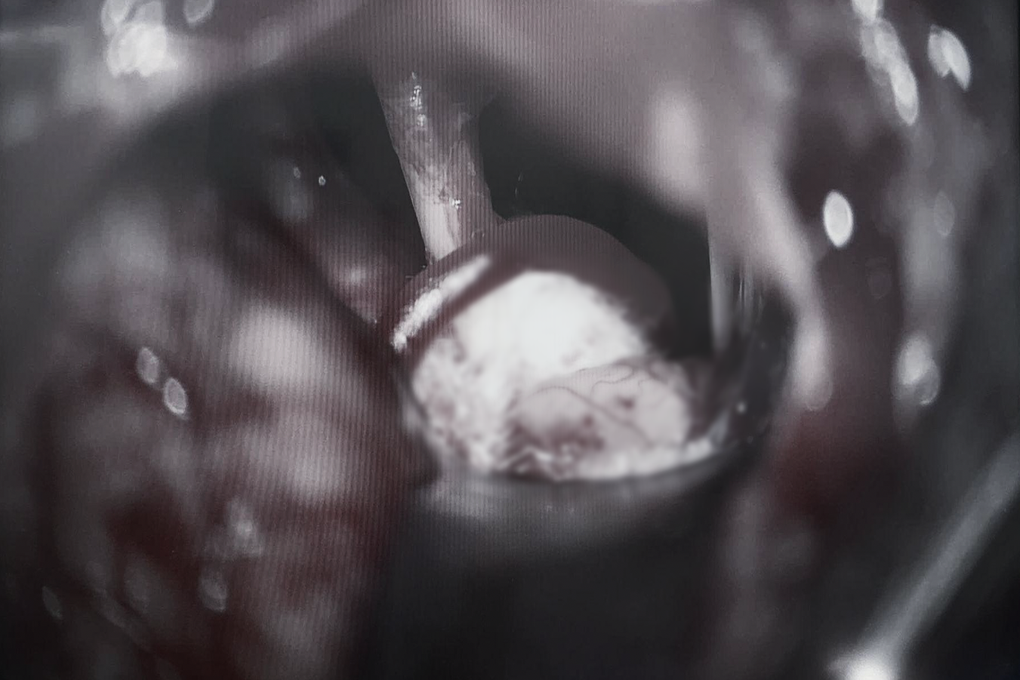

Ca mổ kéo dài hơn 1 giờ do ThS.BS.CKII Đỗ Anh Vũ cùng ê-kíp khoa Gây mê hồi sức trực tiếp thực hiện. Từ một đường rạch da 4cm và mở sọ nhỏ, các bác sĩ tiếp cận vùng tiểu não và quai động mạch chèn ép gốc dây thần kinh số VII.

Ê-kíp đã khéo léo đặt những miếng đệm Teflon – chất liệu y khoa an toàn tạo “lớp đệm cách ly” vĩnh viễn giữa mạch máu và dây thần kinh.

Mọi thao tác được tiến hành tỉ mỉ dưới kính hiển vi phẫu thuật có hỗ trợ nội soi hiện đại, giúp bác sĩ giải phóng chèn ép mà vẫn bảo tồn tối đa các cấu trúc thần kinh quan trọng xung quanh.

Đây là giai đoạn căng thẳng nhất của ca mổ, bởi chỉ một sai lệch nhỏ trong thao tác cũng có thể gây tổn thương dây thần kinh số VII, dẫn đến yếu hoặc liệt mặt sau phẫu thuật.

Miếng đệm Teflon được đặt giữa mạch máu và dây thần kinh một cách tỉ mỉ dưới kính hiển vi phẫu thuật (Ảnh: BV).

Nhờ kinh nghiệm của cả ê-kíp cùng hệ thống kính hiển vi phẫu thuật hiện đại, ca mổ đã diễn ra an toàn và thành công.